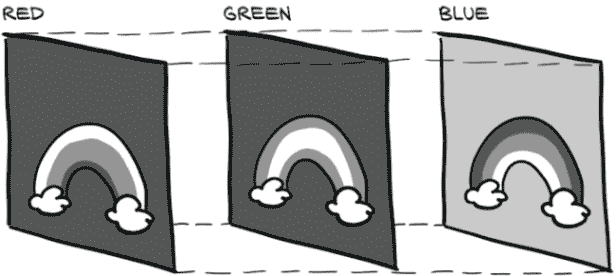

我们生成的数据将是具有多个通道的二维 CT 切片。额外的通道将保存相邻的 CT 切片。回想图 4.2,这里显示为图 13.12;我们可以看到每个 CT 扫描切片都可以被视为二维灰度图像。

图 13.12 CT 扫描的每个切片代表空间中的不同位置。

我们如何组合这些切片取决于我们。对于我们分类模型的输入,我们将这些切片视为数据的三维数组,并使用三维卷积来处理每个样本。对于我们的分割模型,我们将把每个切片视为单个通道,生成一个多通道的二维图像。这样做意味着我们将每个 CT 扫描切片都视为 RGB 图像的颜色通道,就像我们在图 4.1 中看到的那样,这里重复显示为图 13.13。CT 的每个输入切片将被堆叠在一起,并像任何其他二维图像一样被消耗。我们堆叠的 CT 图像的通道不会对应颜色,但是二维卷积并不要求输入通道是颜色,所以这样做没问题。

图 13.13 摄影图像的每个通道代表不同的颜色。

对于验证,我们需要为每个具有正面掩模条目的 CT 切片生成一个样本,对于我们拥有的每个验证 CT。由于不同的 CT 扫描可能具有不同的切片计数,我们将引入一个新函数,将每个 CT 扫描及其正面掩模的大小缓存到磁盘上。我们需要这样做才能快速构建完整的验证集大小,而无需在Dataset初始化时加载每个 CT。我们将继续使用与之前相同的缓存装饰器。填充这些数据也将在 prepcache.py 脚本中进行,我们必须在开始任何模型训练之前运行一次。